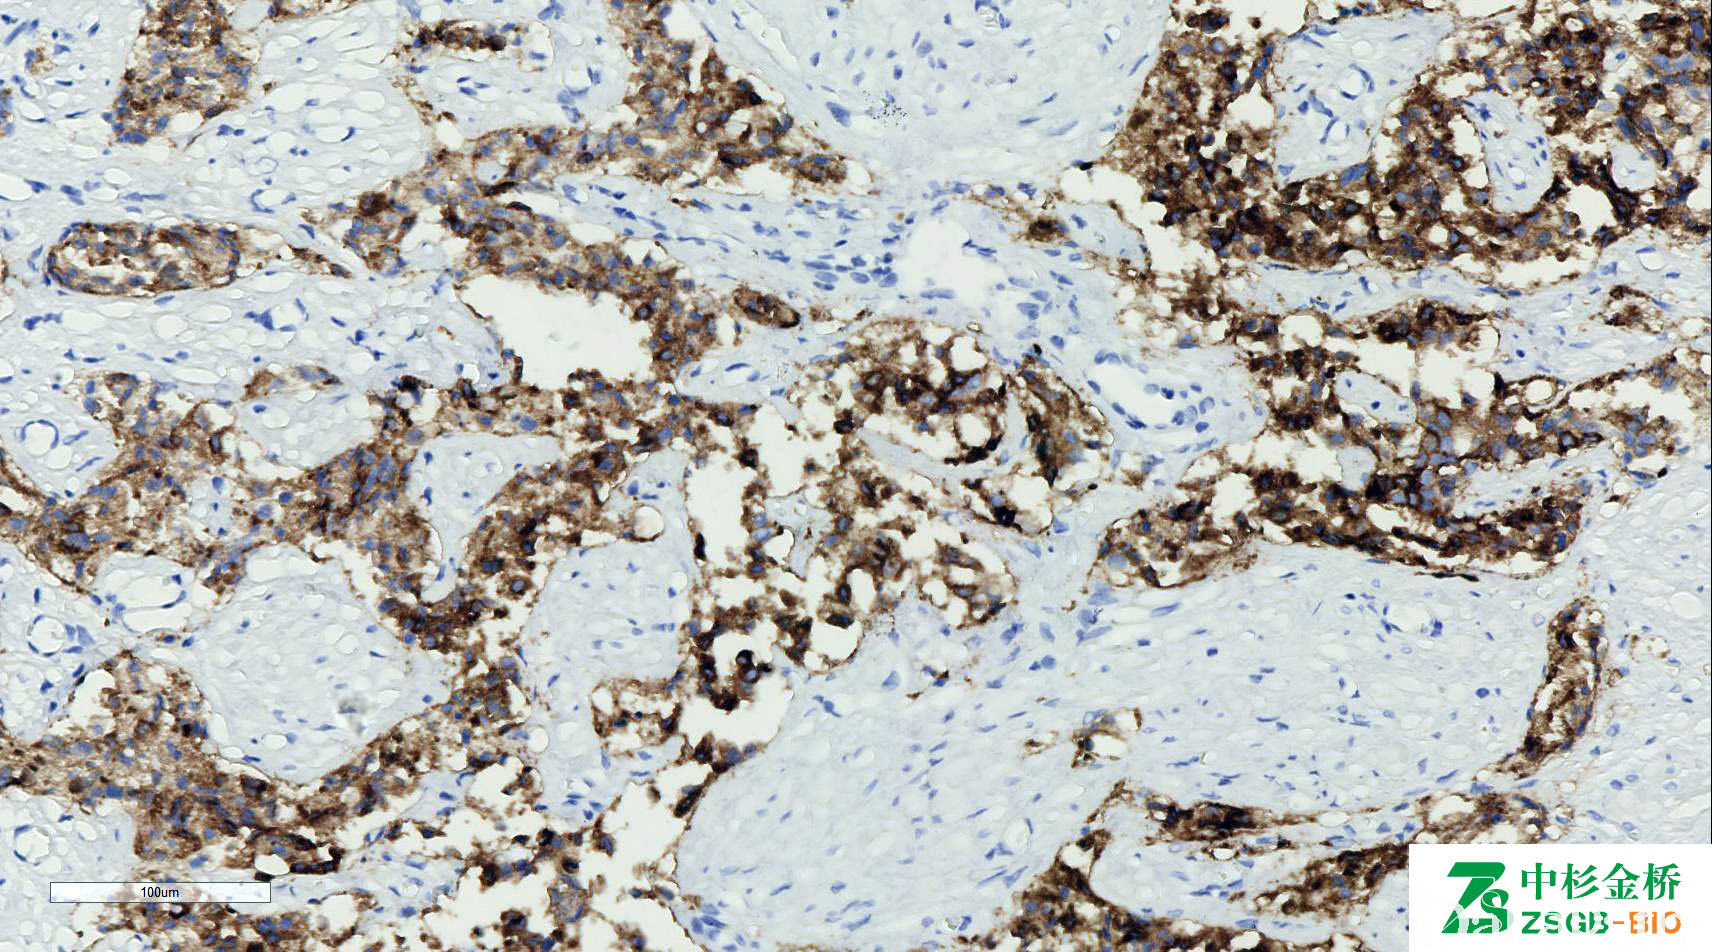

PSA

别名: 前列腺特异性抗原

信号定位: 胞质

几乎全部阳性(≥95%的病例阳性): 腺样囊性癌、前列腺导管腺癌、前列腺癌,≥gleason8 分